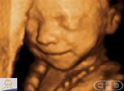

Roteiro: 19 週以降の胎児の動きでは 呼吸活動が始まり 心拍は日周性の 概日リズムに支配されます |

Todas as idades fizeram referência a fecundação, não ao último período menstrual.

Um mês = 4 semanas.